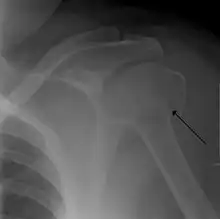

Fracture of the greater tuberosity of the humerus -

Multi-fragmented, or comminuted fracture of the proximal humerus with involvement of the greater tuberosity -